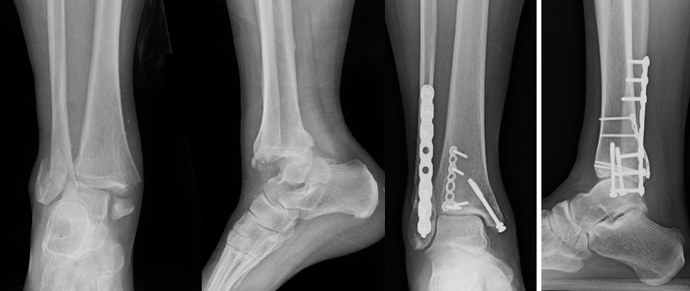

3. Syndesmotic Instability

Syndesmotic injury is a key driver of ankle instability. Clinical examination, radiographic parameters (ie, decreased tibia-fibula overlap), and a thorough intraoperative assessment guide the need for stabilization. There are various ways to stress the syndesmosis including the hook test, which has been shown to be somewhat unreliable in determining syndesmotic instability.12 Arthroscopic evaluation of the syndesmosis provides a reliable evaluation of the syndesmosis.13 However the method of testing the integrity of the syndesmosis, it is important to highlight the necessity of fixation when indicated, as shown by Pogliacomi and colleagues in 2021.14 Meta-analyses of randomized trials show suture-button fixation provides equivalent or improved functional outcomes with lower reoperation rates compared with syndesmotic screws, particularly by avoiding routine hardware removal.15-17 Syndesmotic instability is a critical determinant of ankle fracture stability, requiring careful clinical, radiographic, and sometimes arthroscopic assessment to guide fixation (Figure 3).